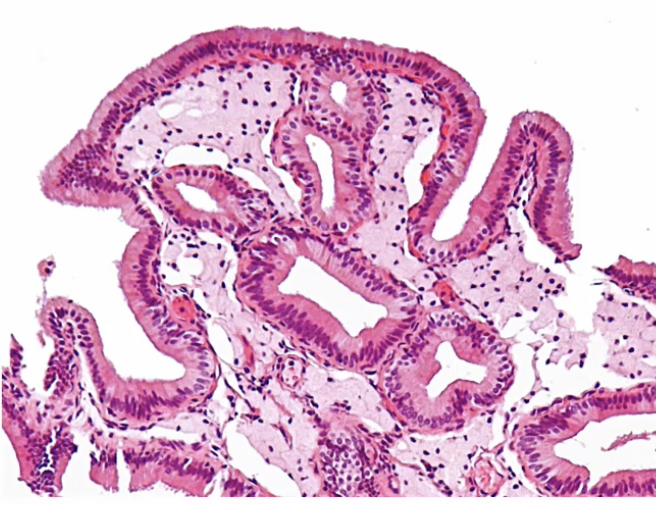

Follicular Cholecystitis